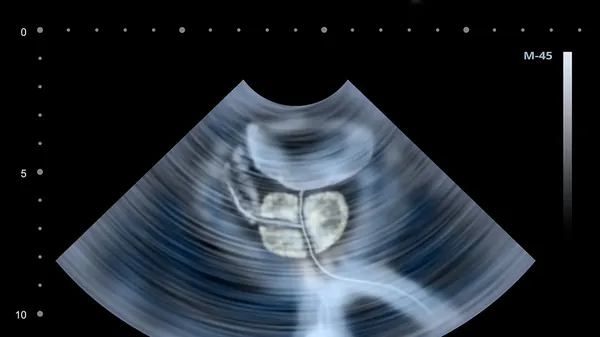

L’AUTOPSIA. Nel corso della mattinata di lunedì 15 settembre l’autopsia sul corpo di Francesca Pettinato, trovata mummificata in casa a un anno dalla morte. La figlia di 61 anni accusata di occultamento del cadavere e truffa. Parla l’avvocato difensore.